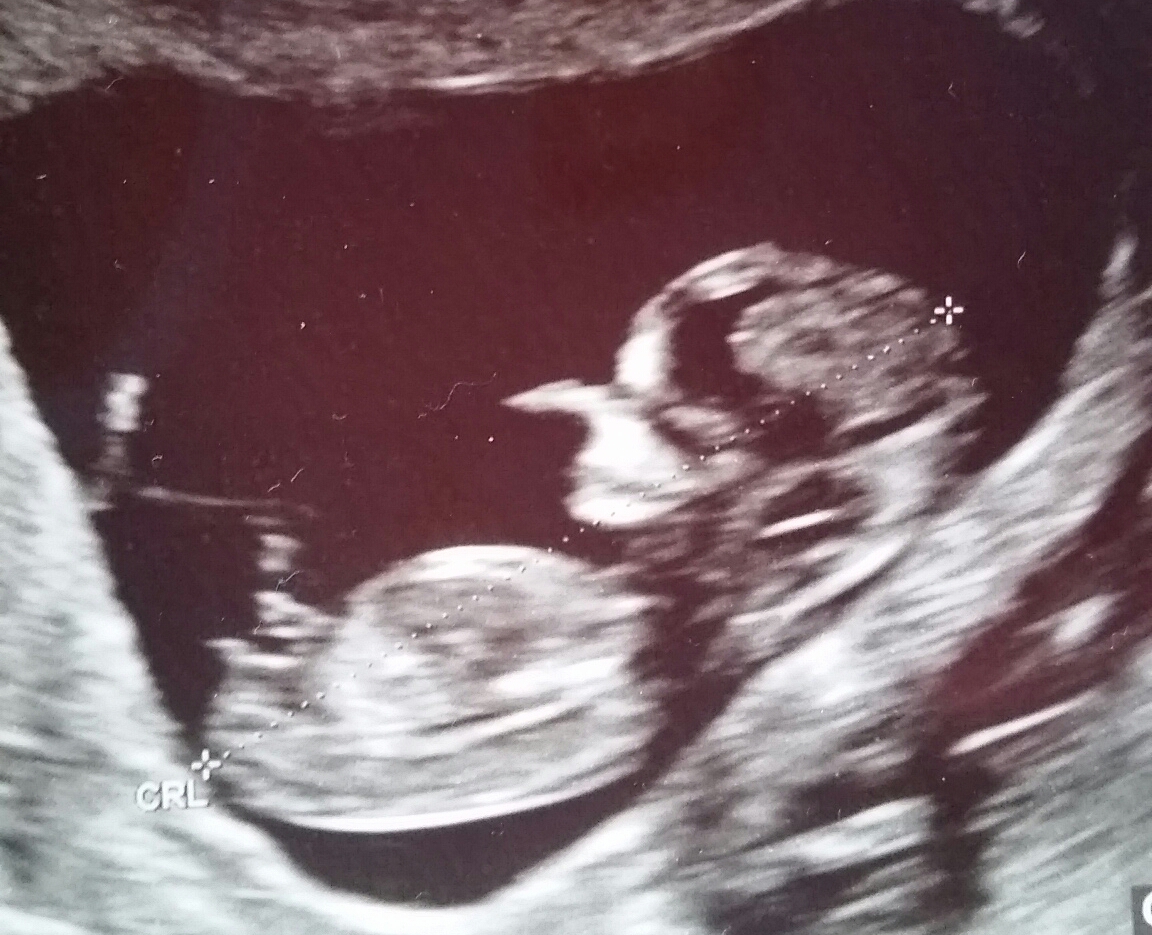

First picture is 12 wks 5days, second one is 13 wks.

I've looked at tons of these ultrasounds, and I still don't understand -- what makes this one "stacked" and not just a "fork" at a different angle? Even though the nub is pretty parallel to the spine, you'd still guess boy?

Difficult one here, since the second nub seems to be parallel to the spine, and it's a later gestation (13 weeks) than the very boyish nub at 12+4.... I have to say 50/50.